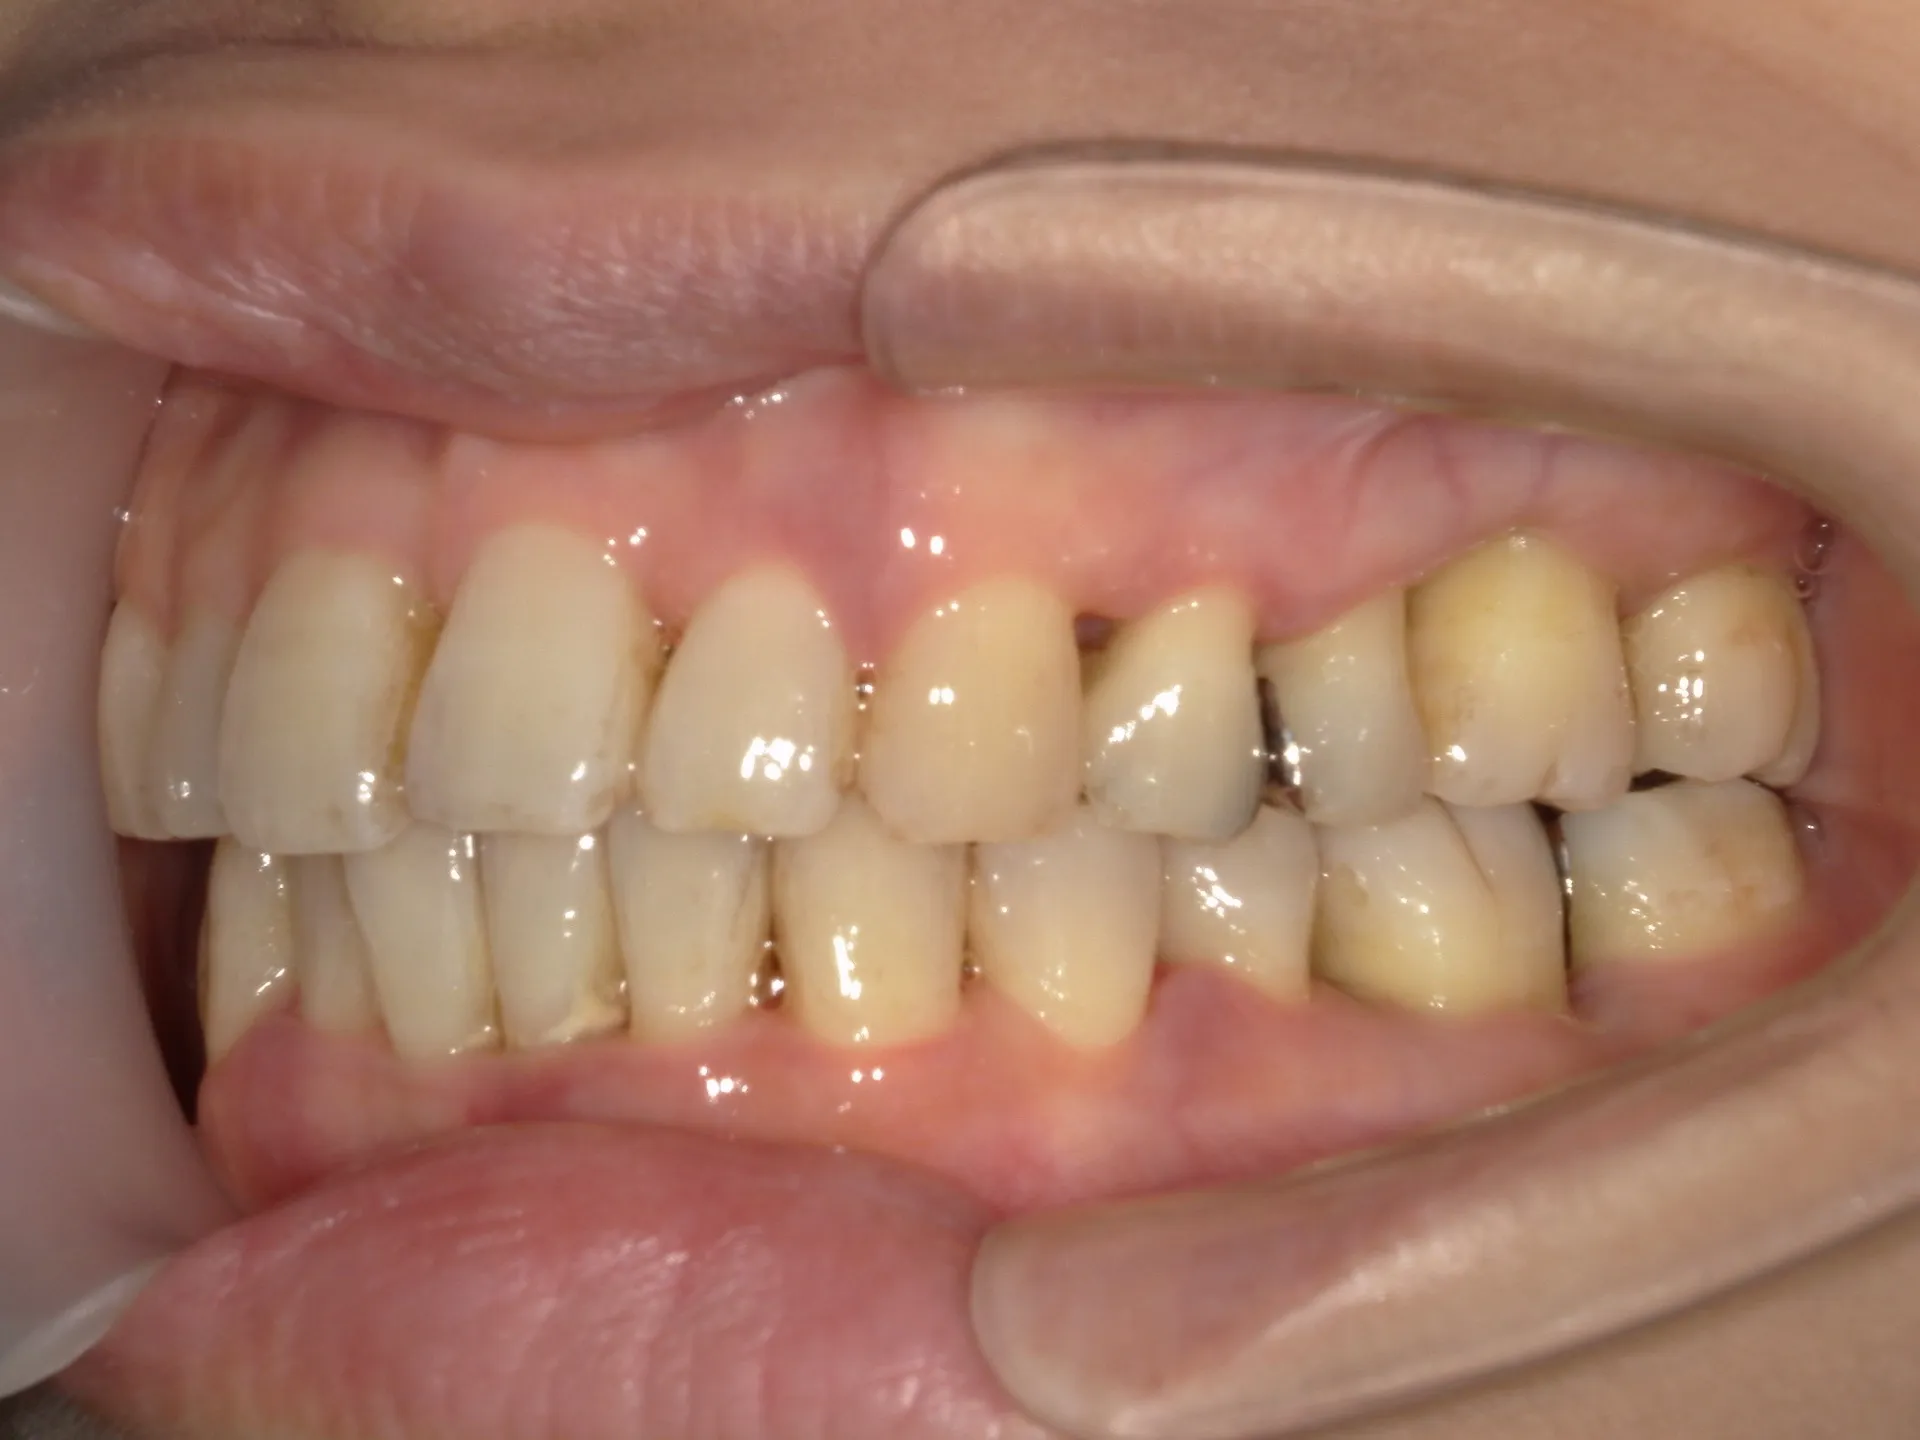

当院では矯正治療と歯周治療を平行して行うことにより矯正治療を進めていけることができました。

しかしながら、今回の治療途中で歯茎が腫れるなどの影響もあり、歯周治療中の矯正治療はリスクであることは患者様にも初回の段階で説明していることもあり、患者様もこの状態の歯並びで満足しており、歯を残すためにも今回は矯正治療を中断する希望をされました。